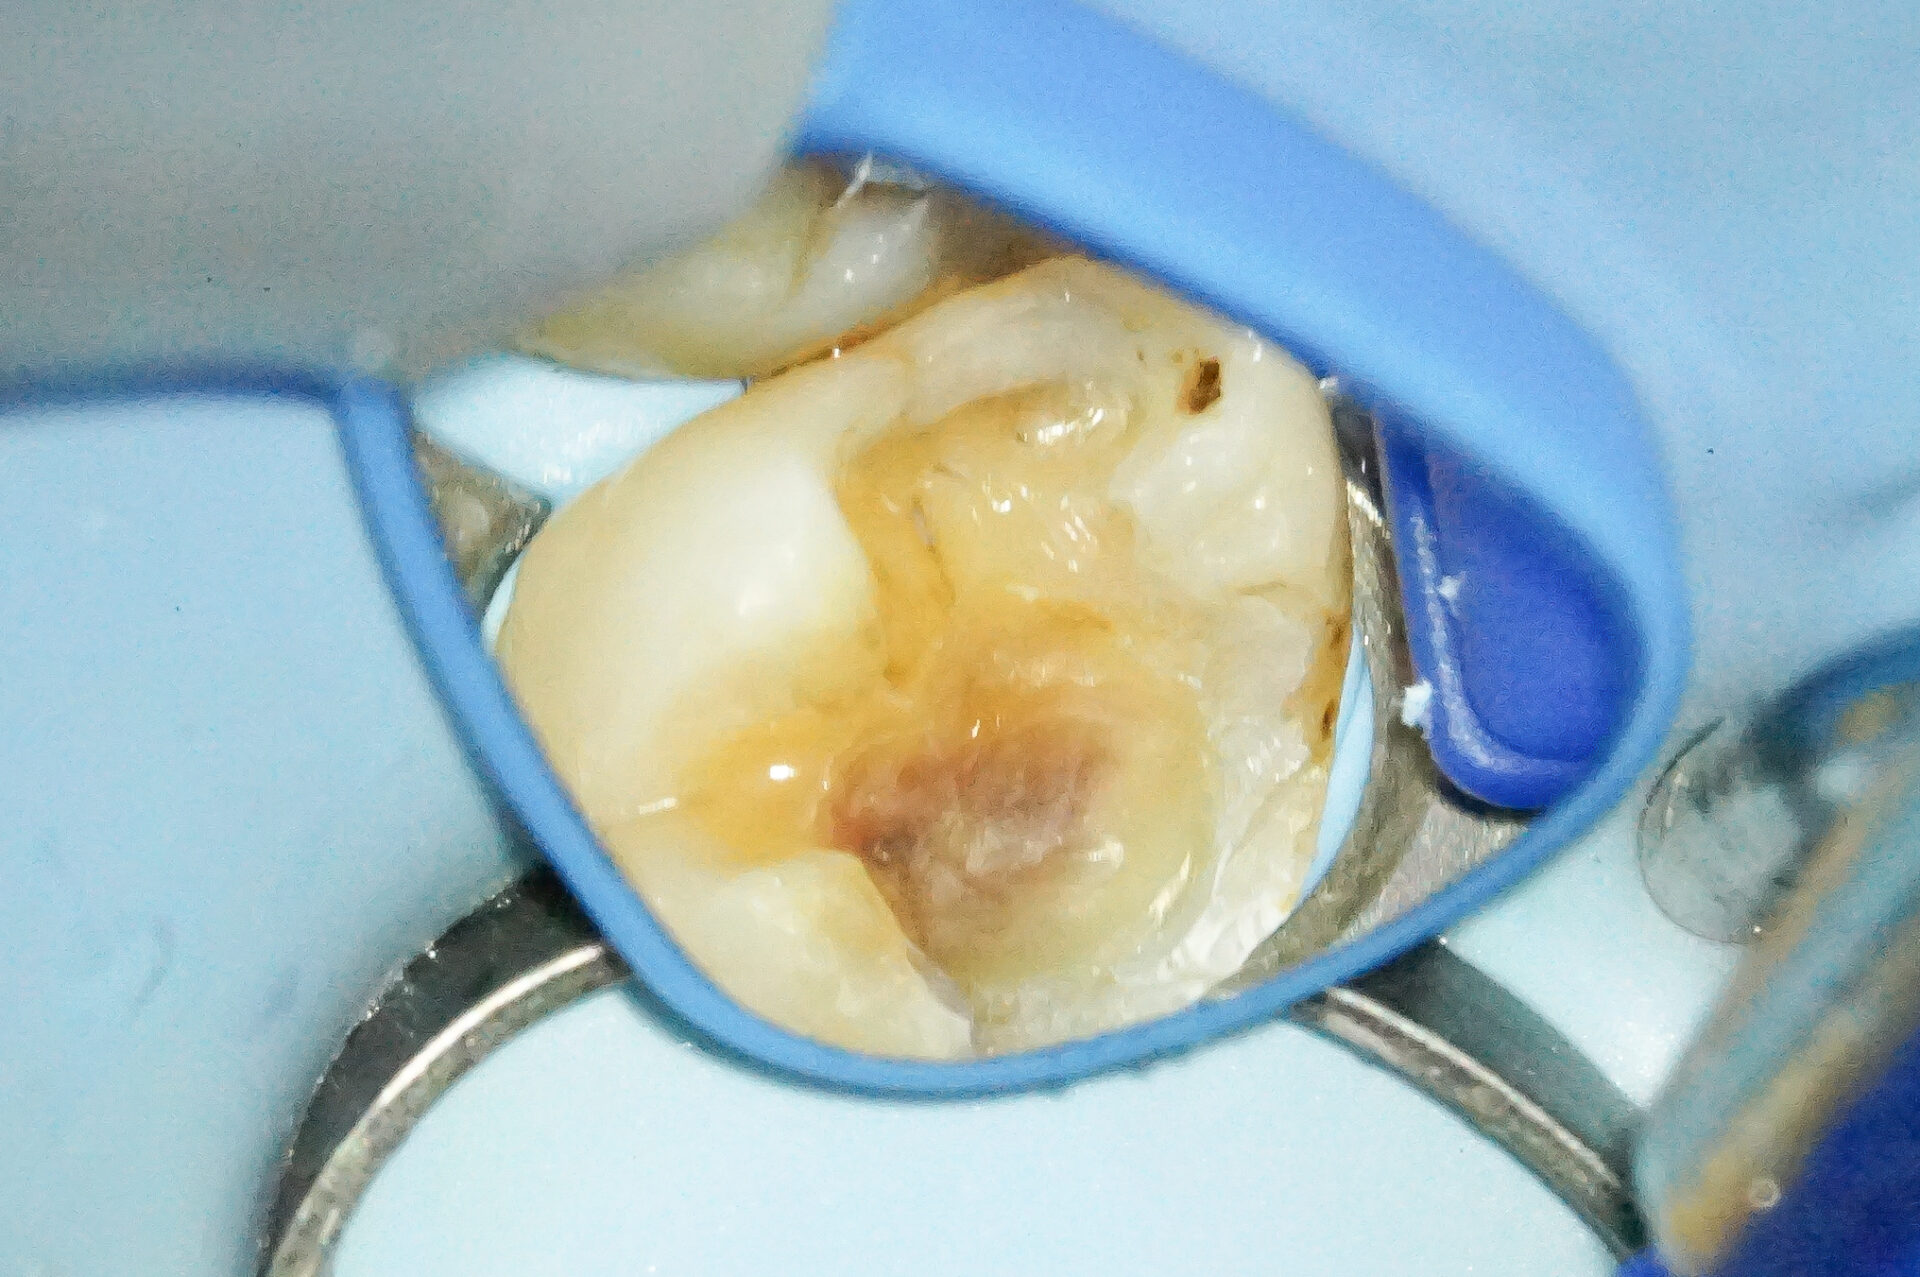

ウ蝕検知液で染めたところ、ピンク色に染まります。

染まるところがウ蝕(虫歯)です。

マイクロスコープで丁寧に観察すると歯の破折が見られました。

可及的に掘り進め、歯へのダメージを最小限に、尚且つクラック部からの細菌感染の防止ができるように作業を行いました。

ここでウ蝕やクラックを取り残してしまうと数年後に再発してしまいます。同じセラミック治療でも長期にわたってトラブルが発生しないようにするためにはこのような繊細な治療が必要です。